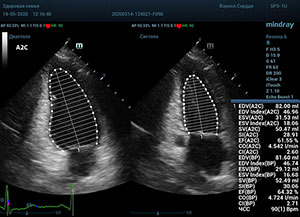

С появлением В режима реализовалась возможность визуализации всех сегментов миокарда из парастернальных и апикальных сечений. Метод Teicholtz в широкой практике сменился методом дисков. Метод дисков, или метод Simpson, позволяет разбить левый желудочек на 20 дисков, с расчетом объема каждого из них. Используя 2 перпендикулярных сечения, апикальные двух и четырех камерное, мы приближаемся к значению реального объема левого желудочка. Исследователь обводит интерфейс эндокард – кровь в фазу диастолы и фазу систолы. Линия простирается от кольца митрального клапана и до кольца митрального клапана, четко разграничивая объем желудочка от предсердия. Для достоверного изменения необходимо использовать ЭКГ канал.

Что могут предложить современные приборы? Приборы нашего времени являются мощными вычислительными машинами, способными обрабатывать полученную информацию даже без помощи человека. Система автоматического вычисления фракции выброса – AUTO EF на приборах серии Resona компании Mindray сделает все за вас. За пару секунд прибор сам отыщет нужную фазу сердечного цикла и произведёт измерение и расчеты, а также покажет график изменения объема в сердечном цикле. От Вас требуется только получить качественное 4С и 2С сечение. Впрочем, прибор всегда оставляет возможность коррекции, если доктор имеет свое мнение на расположение точек планиметрии или момента измерения по ЭКГ каналу.